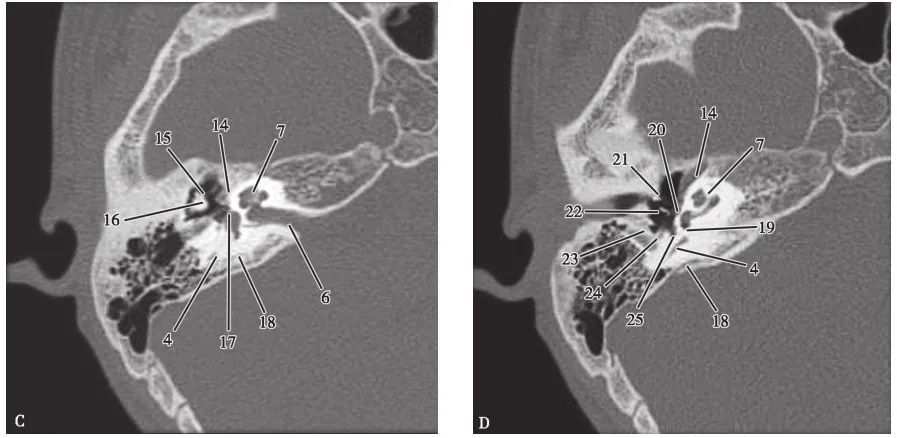

耳部及其周围的重要解剖结构 (CT横断面)

A.上骨半规管层面;B.外骨半规管层面;C.前庭窗层面;D.耳蜗层面;E.颈动脉管层面1.上骨半规管;2.弓形下窝;3.总骨脚;4.后骨半规管;5.外骨半规管;6.内耳道;7.耳蜗;8.面神经管迷路段;9.膝状神经节;10.前庭;11.上鼓室;12.乳突窦入口;13.乳突窦;14.鼓膜张肌;15.锤骨头;16.砧骨体;17.前庭窗;18.前庭导水管;19.圆窗;20.鼓岬;21.锤骨颈;22.砧骨长脚;23.面神经隐窝;24.锥隆起;25.鼓室窦;26.颈动脉管;27.咽鼓管;28.耳蜗导水管;29.颈静脉球